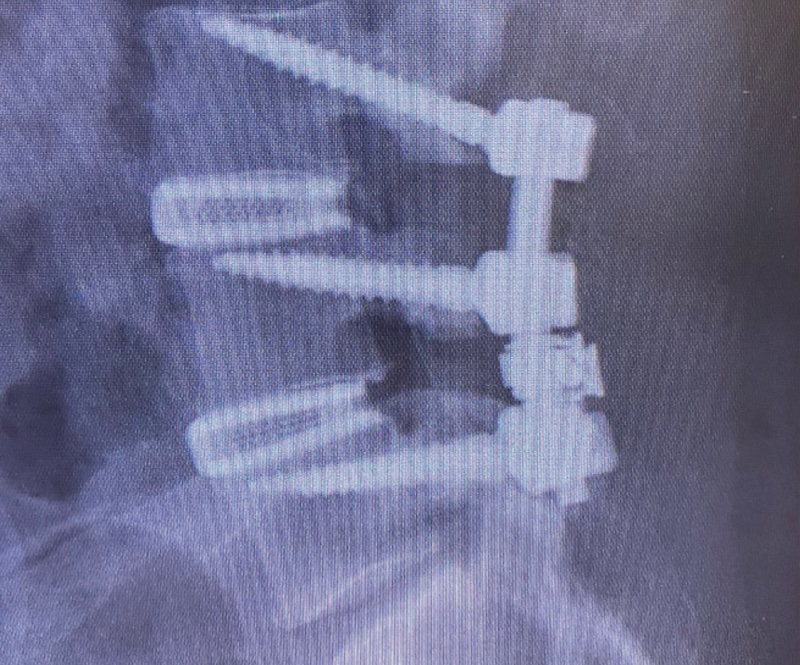

The Juliett Ti PO by Spineart is a 3D printed porous titanium lumbar interbody spacer for use singly or bilaterally in the PLIF procedure. They feature Ti-LIFE proprietary 3D printed technology to mimic cancellous bone to promote bony ingrowth and faster fusion. It features a roughened porous and lattice surface with a smooth bullet nose for endplate distraction and easy insertion.